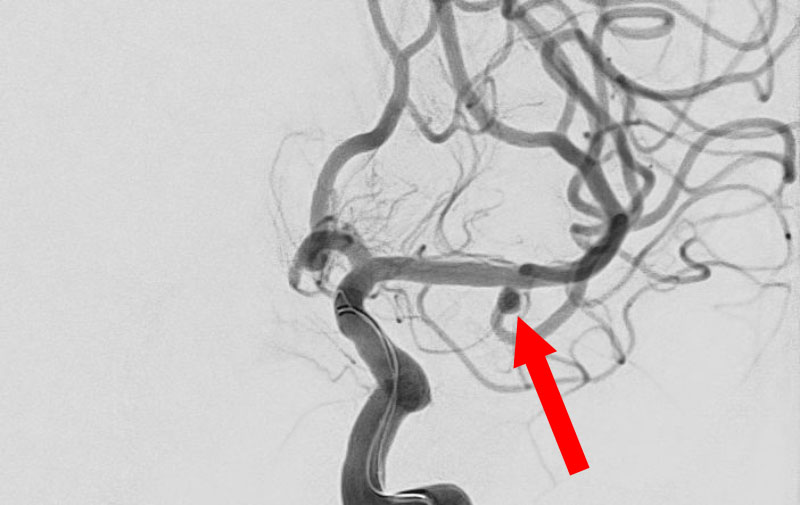

No.1596 手術前

くも膜下出血

左中大脳動脈瘤破裂

40代

救急外来